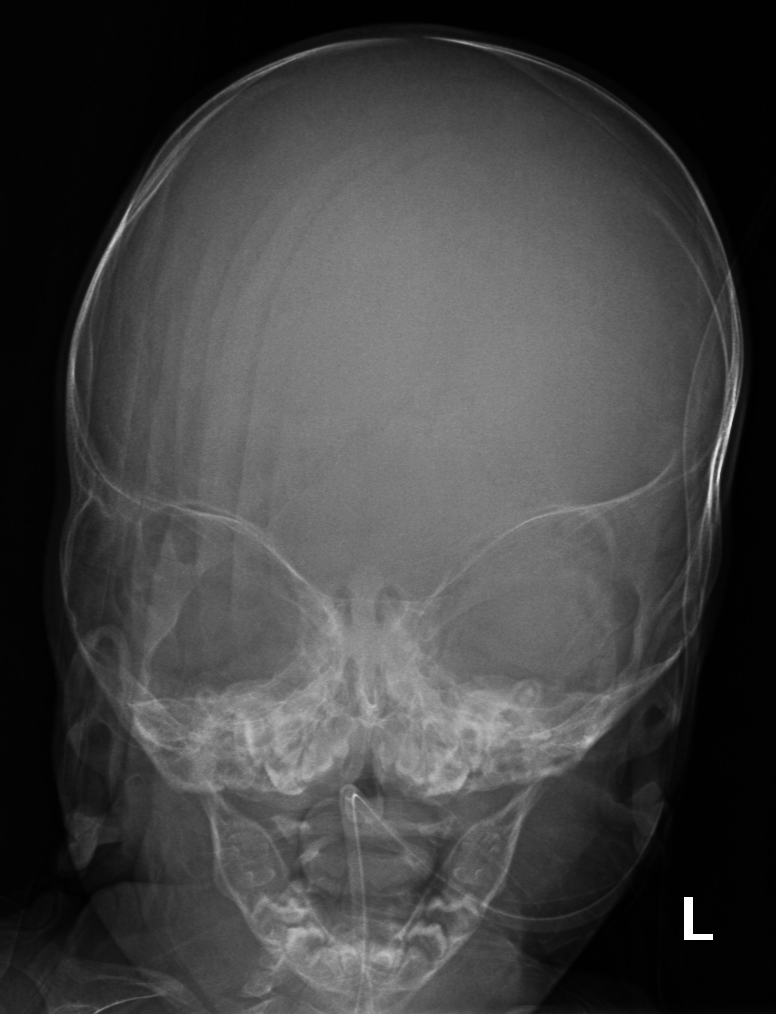

El diagnóstico del Síndrome de Apert se basa en un examen físico detallado, radiografías y pruebas genéticas para identificar la mutación en el gen FGFR2. El tratamiento implica cirugía para corregir craneosinostosis y deformidades en manos y pies. Es crucial la intervención de equipos médicos multidisciplinarios especializados en cirugía craneofacial y genética.

- Craneosinostosis: Cierre prematuro de las suturas craneales, evidenciado por crestas a lo largo de las suturas.

El Síndrome de Apert es un trastorno genético autosómico dominante causado por una mutación espontánea en el gen FGFR2, específicamente en el receptor 2 del factor de crecimiento de los fibroblastos. Esta anomalía genética provoca el cierre prematuro de las suturas entre los huesos del cráneo, una condición conocida como craneosinostosis, afectando la forma de la cabeza y la cara2.